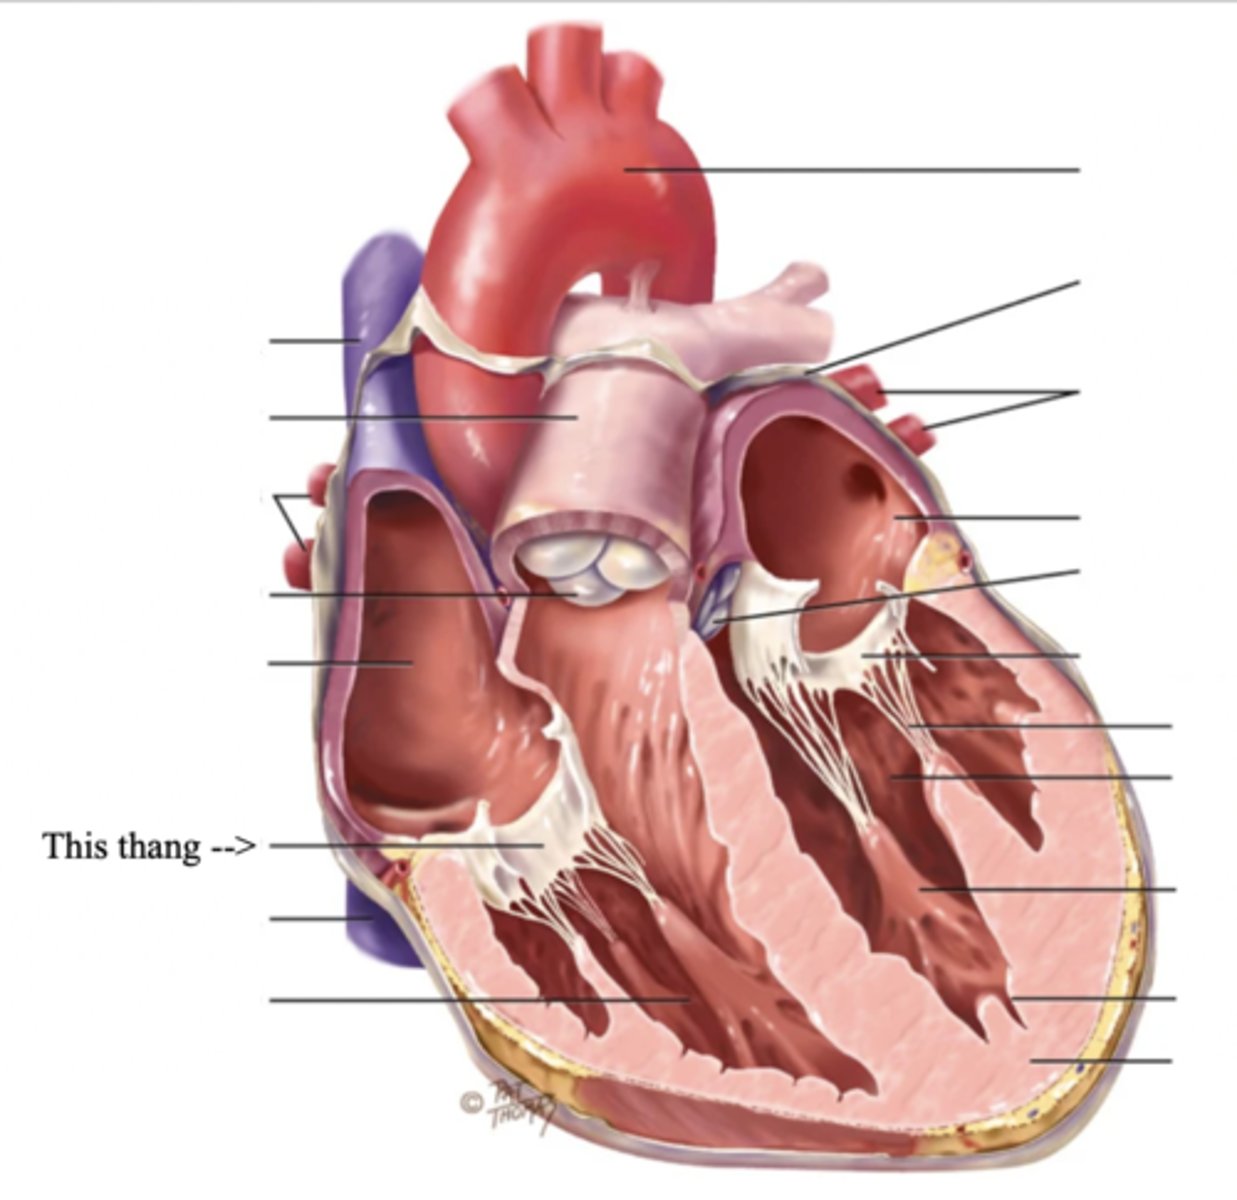

Anatomy of the Heart

Myocardium

The muscular wall of the heart; does the pumping

Endocardium

The thin layer of endothelial tissue that lines the inner surface of the heart chambers and valves

2 Types of Chambers in the Heart

- Atrium

- Ventricles

Atrium (2)

A thin-walled reservoir for holding blood, located at the upper chamber of the heart

Ventricle (2)

The thick walled muscular pumping chamber of the heart located at the bottom chamber of the heart

2 Main Types of Valves of the Heart

- Atrioventicular

- Semilunar

Atrioventricular Valves (AV) (2)

The valves that separate the atria and the ventricles

The 2 Atrioventicular Valves of the Heart

- Tricuspid

- Mitral

Tricuspid Valve

- The right AV valve separating the right atrium from the right ventricle

- Connected by 3 chordae tendinae

Mitral (Bicuspid) Valve

- The left AV valve separating the left atrium from the left ventricle

- Connected by 2 chordae tendinae

Chordae Tendinae

Fibers (heart strings) attatched to the tricuspid and mitral valve which pull it closed when papillary muscles contract, preventing back flow of blood

Semilunar Valves (SV) (2)

Valves located between the ventricles and the pulmonary arteries and aorta

The 2 Semilunar Valves of the Heart

- Pulmonic

- Aortic

Pulmonic Valve

The SV valve of the right side of the heart

Aortic Valve

The SV valve of the left side of the heart

The 4 Great Vessels of the Heart

- Superior/inferior venae cavae

- Pulmonary artery

- Pulmonary veins

- Aorta

Superior/Inferior Venae Cavae

The large veins that empty into the right atrium of the heart and return unoxygenated venous blood to the right side of the heart

Pulmonary Artery

Artery carrying oxygen-poor blood from the heart to the lungs

Pulmonary Veins

Veins carrying oxygenated blood from the lungs to the heart

Aorta

The largest artery in the body which carries oxygenated blood from the heart throughout the body